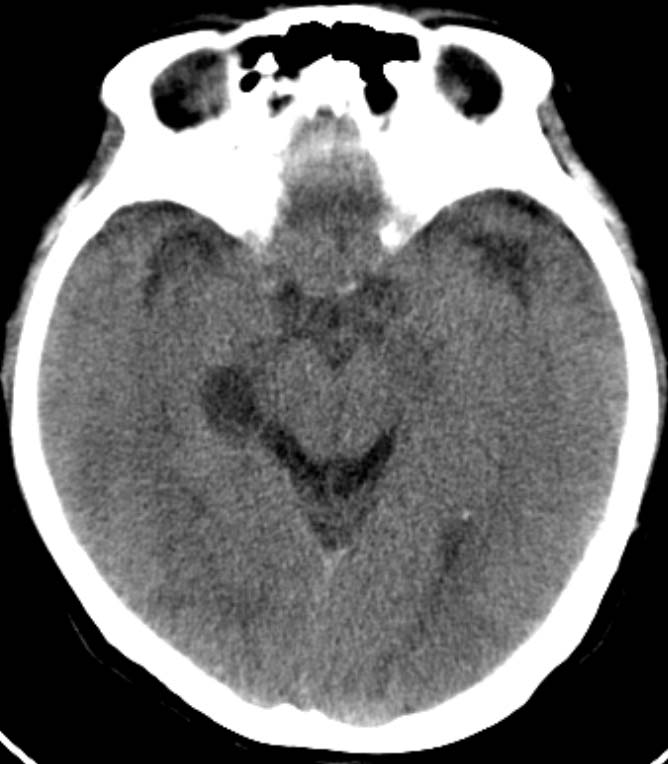

标题: CT16631:女,46岁,头痛数月。 [打印本页]

标题: CT16631:女,46岁,头痛数月。

女,46岁,头痛数月。求助战友。。。。。。。。。。。。

其余颅脑层面未见异常。

考虑脉络裂囊肿或蛛网膜囊肿可能,建议加薄扫

支持 右侧脉络膜裂囊肿。

右侧脉络膜囊肿可能性大

mri结果为考虑:蛛网膜囊肿